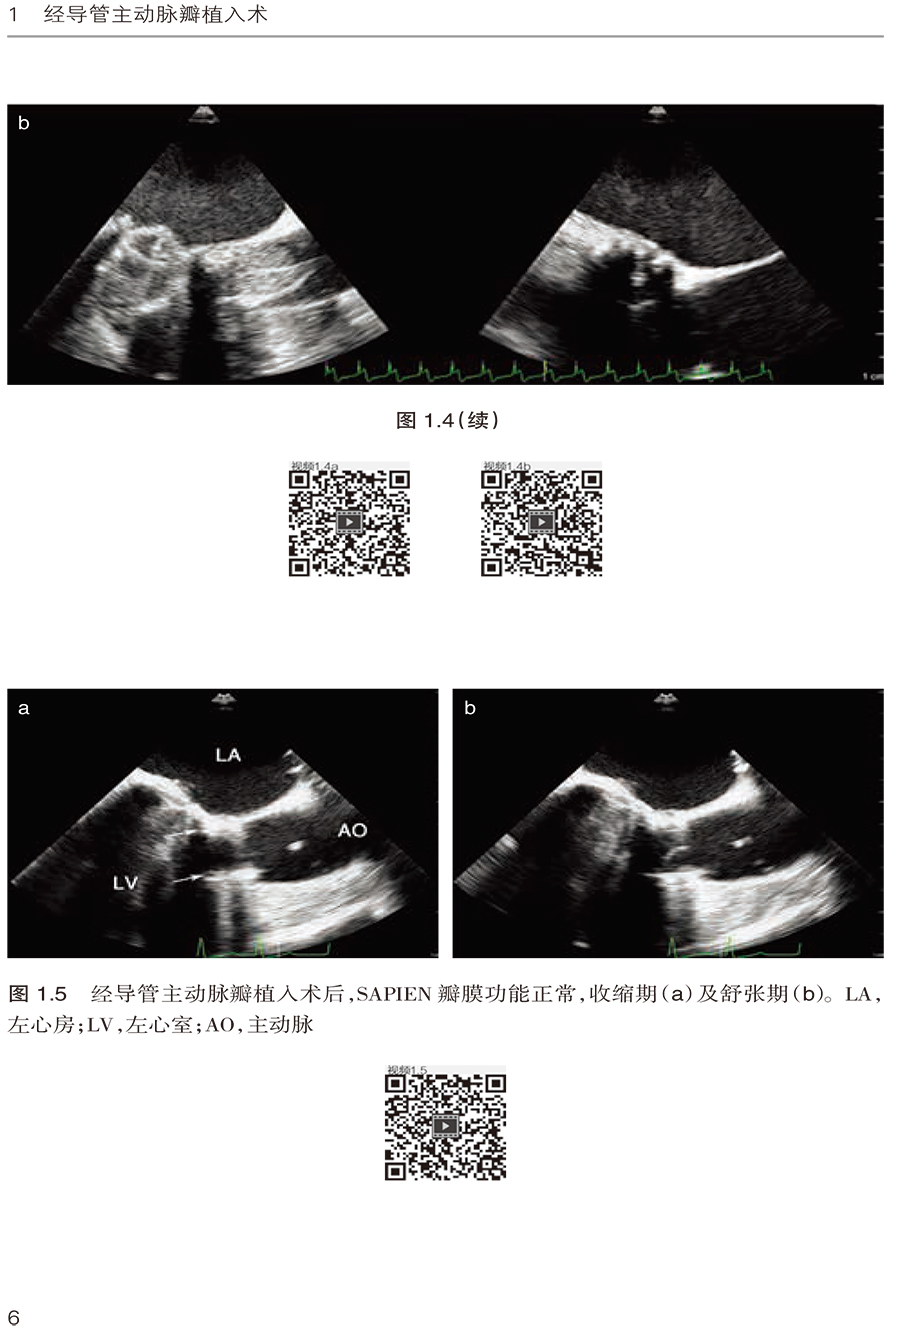

1.2 经心尖SAPIEN 瓣膜植入术 /3